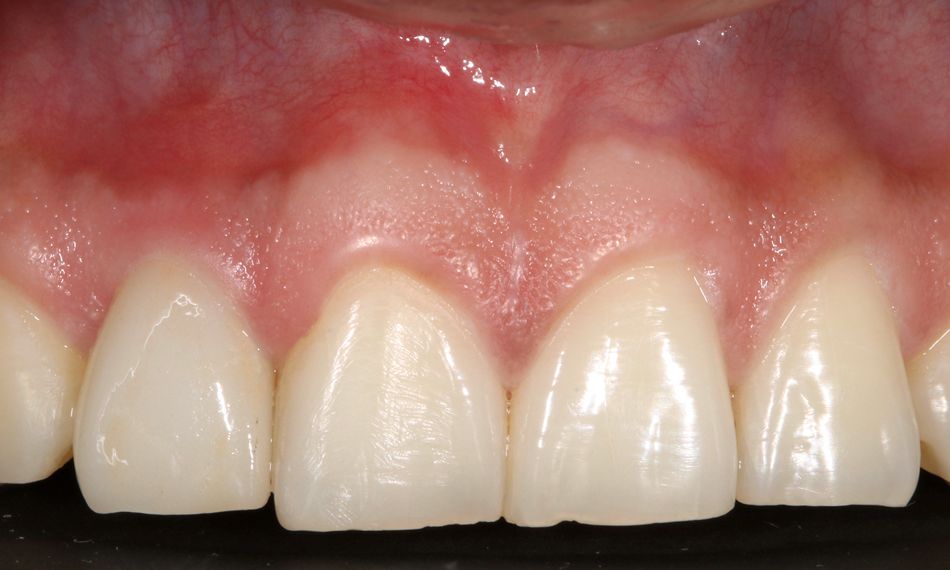

The patient was very satisfied with the implant placement procedure and the opportunity to receive a restoration promptly following the extraction of his anterior tooth (Figs. 31-33). The patient was enrolled in an annual maintenance program.

The final outcome resulted in health maintenance in the hard and soft tissues.